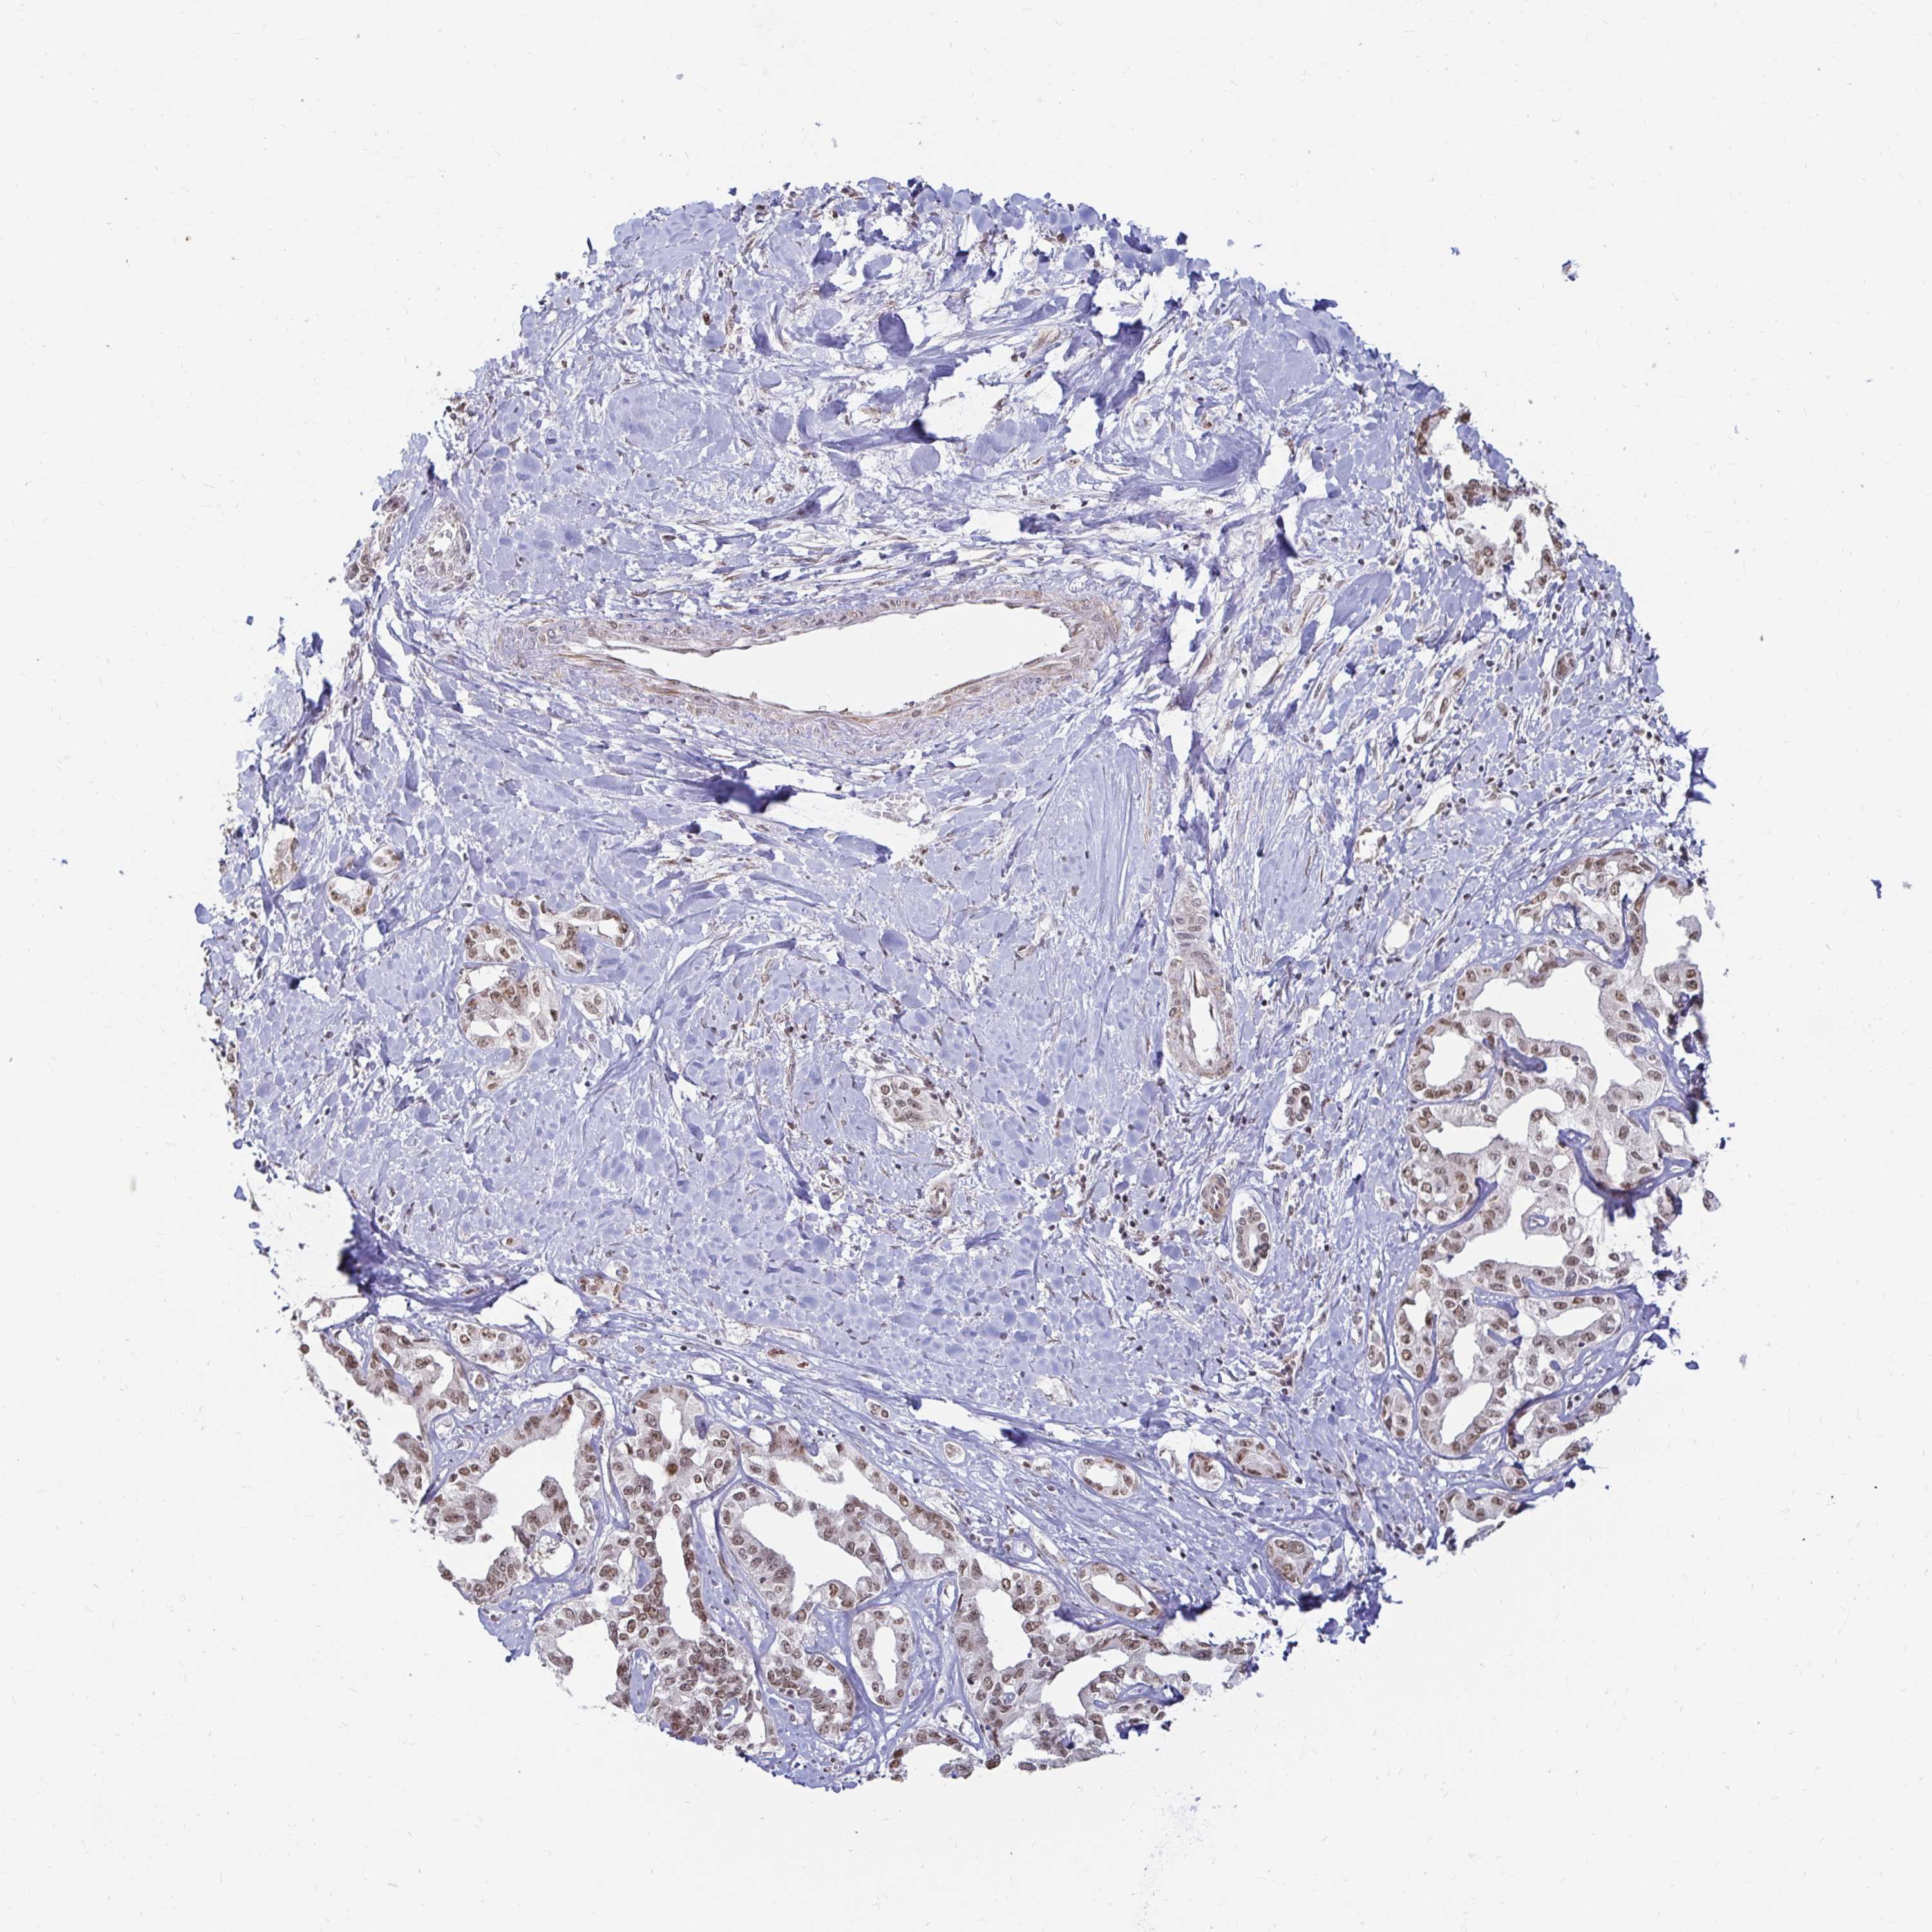

LIVER CANCER - Protein expressioni

A mouse-over function shows sample information and annotation data. Click on an image to view it in a full screen mode. Samples can be filtered based on level of antibody staining by selecting one or several of the following categories: high, medium, low and not detected. The assay and annotation is described here.

Note that samples used for immunohistochemistry by the Human Protein Atlas do not correspond to samples in the TCGA dataset.

Antibody stainingi

Antibody staining in the annotated cell types in the current human tissue is reported as not detected, low, medium, or high, based on conventional immunohistochemistry profiling in selected tissues. This score is based on the combination of the staining intensity and fraction of stained cells.

Each image is clickable and will lead to virtual microscopy that enables deeper exploration of all samples and also displays staining intensity scores, fraction scores and subcellular localization as well as patient and tissue information for each sample.

Antibody HPA041057

Antibody HPA058707

Antibody CAB011532

Staining

High

Medium

Low

Not detected

Intensity

Strong

Moderate

Weak

Negative

Quantity

>75%

75%-25%

<25%

None

Location

Nuclear

Cytoplasmic/membranous

Cytoplasmic/membranous,nuclear

Cholangiocarcinoma

Carcinoma, Hepatocellular, NOS